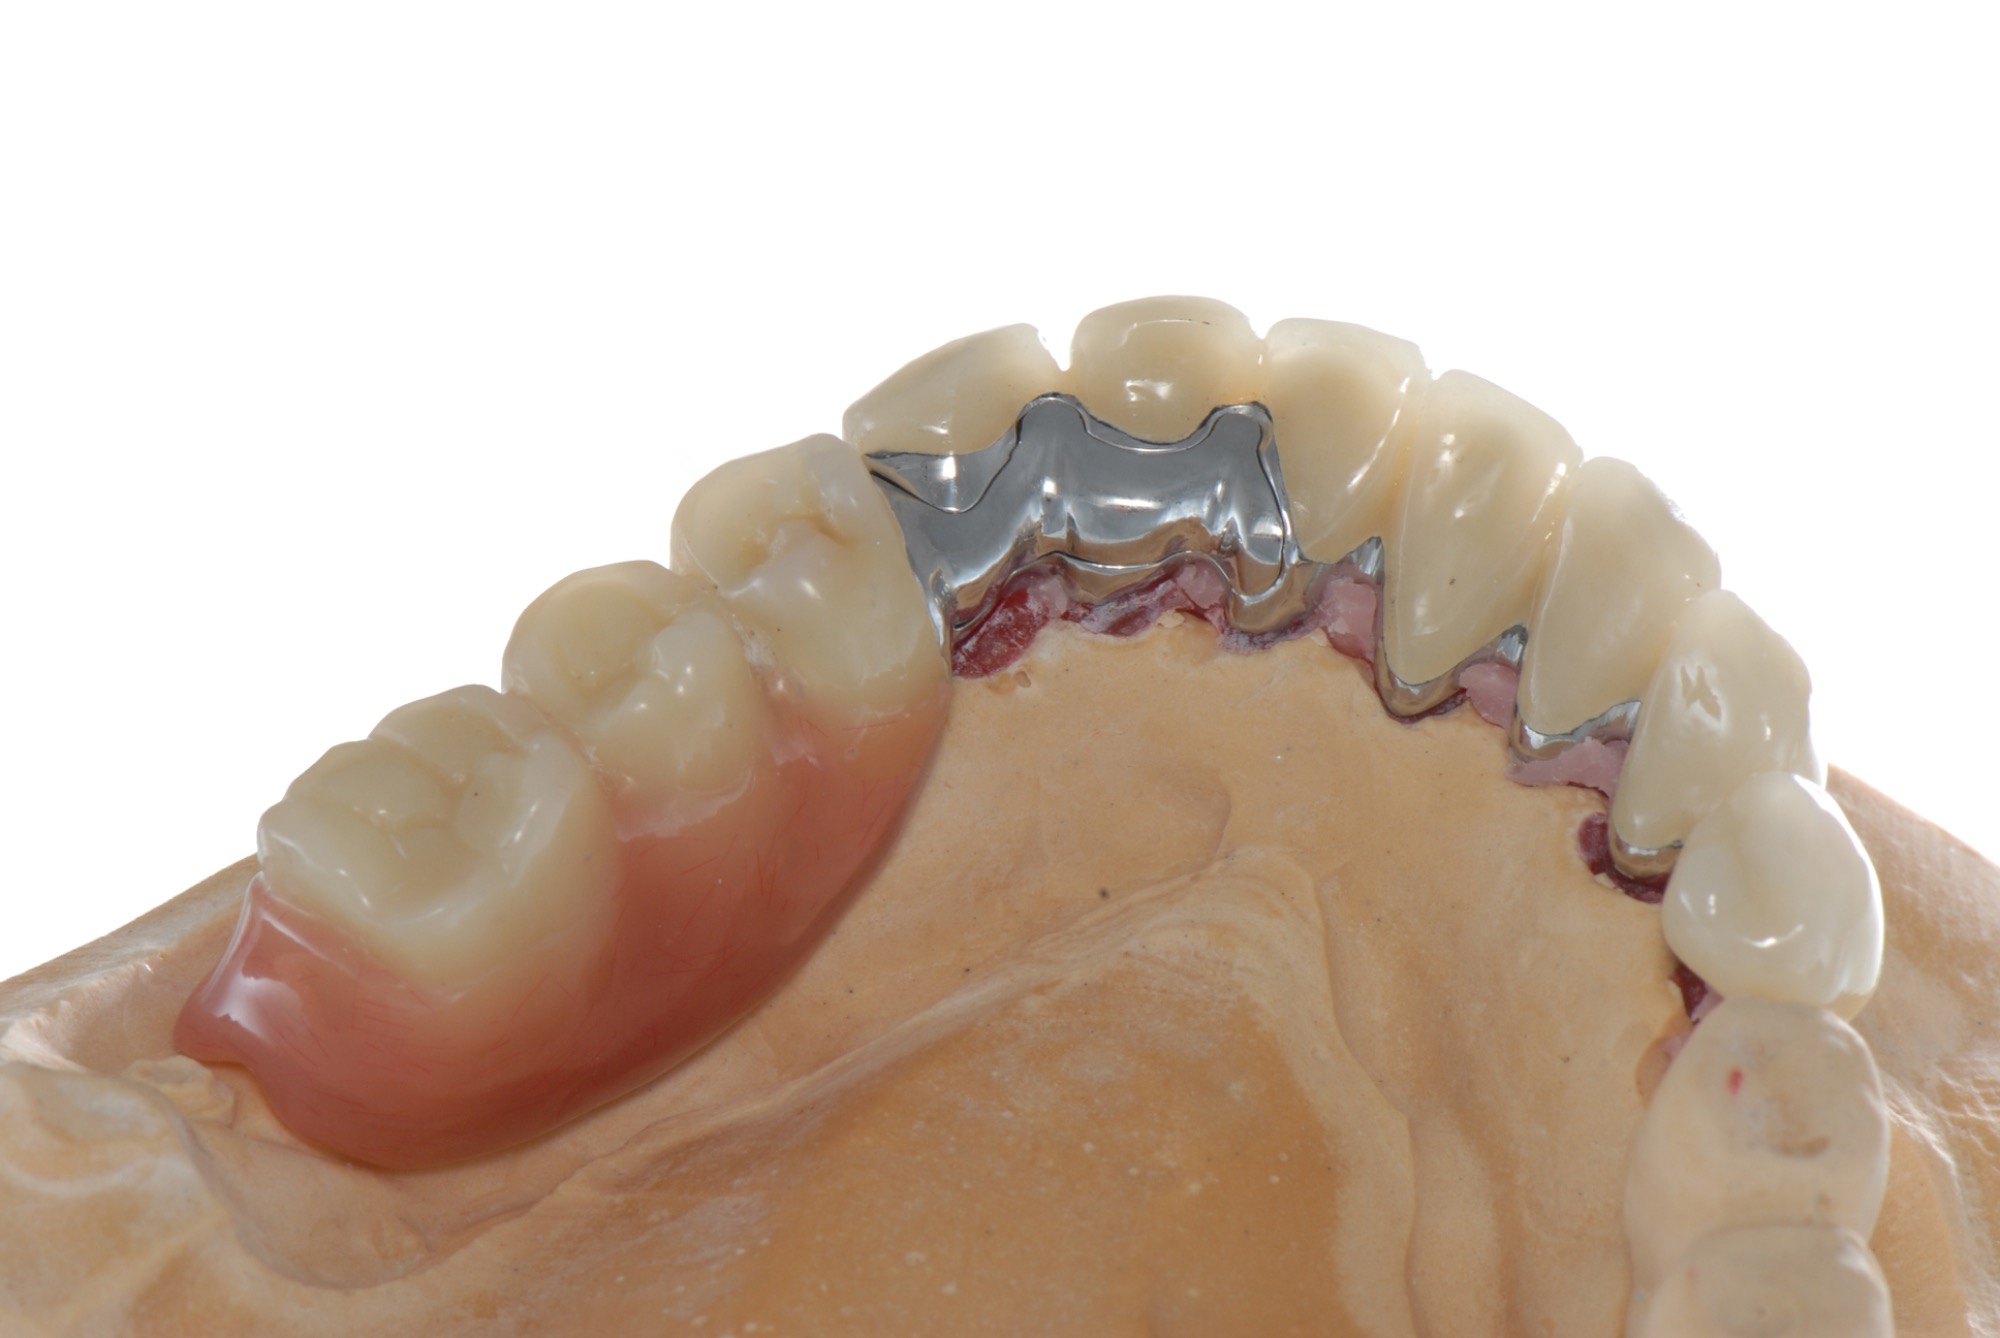

Teleskopierende Oberkieferbrücke. Wie die eigenen Zähne, aber einfach zu reinigen.

Teleskopierende Brücken im digitalen Ablauf hergestellt.